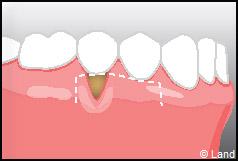

Les greffes de conjonctifs enfouis :

Destinées aux zones esthétiques, elles consistent à prélever la partie profonde du palais (site donneur).

Ce greffon est ensuite inséré sous la gencive au niveau de la récession (site receveur).